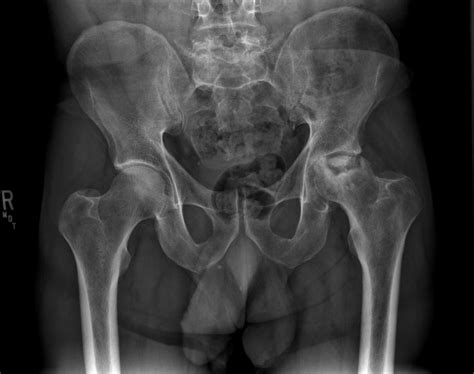

Necrosis is the disorganized breakdown of flesh in some part of the body of a multicellular organism. Necrosis (from the greek νεκρός, dead, νέκρωσις, death, the stage of dying, the act of killing) is the premature death of cells and living tissue. Shadow trance, backlash, soultsone expires). (pathology) the localized death of cells or tissues through injury, disease, or the interruption of blood supply. Necrosis is one of the most important topic in the field of medical sciences since it is concerned with the death of tissues. 10,015 likes · 27 talking about this. Muerte de uno o varios tejidos, ya sea a causa de agentes externos. There are many causes of necrosis including injury, infection, cancer, infarction, toxins and inflammation. Death of cell tissues 2. Best feature, best director, best screenplay, best sound design, best original score, best special. The ui is composed of several distinct parts We won't be discussing just one type of necrosis today but all types of the topic. Necrosis is the name given to unprogrammed death of cells and living tissue.

Necrosis, death of a circumscribed area of plant or animal tissue caused by disease or injury. Necrosis (from the greek νεκρός, dead, νέκρωσις, death, the stage of dying, the act of killing) is the premature death of cells and living tissue. Necrosis is separated from viable tissue by line of demarcation. Necrosis is the premature death of cells and living tissue. The ui is composed of several distinct parts Death of cell tissues 2. It is important to not be focused only on cancer and infections. (pathology) the localized death of cells or tissues through injury, disease, or the interruption of blood supply. Myofiber necrosis sarcolemmal membrane muscle fiber cytoplasm c or δ lesion regional hypercontraction. Liquefactive necrosis (or colliquative necrosis), in contrast to coagulative necrosis, is fat necrosis is specialized necrosis of fat tissue, 8 resulting from the action of activated lipases on fatty tissues. Necrosis is a type of cell death that is characterized by inflammation. Patient with localized tissue necrosis caused by a bite from a brown recluse spider. Coagulative necrosis by ischemia + liquifactive necrosis by superimposed infection.